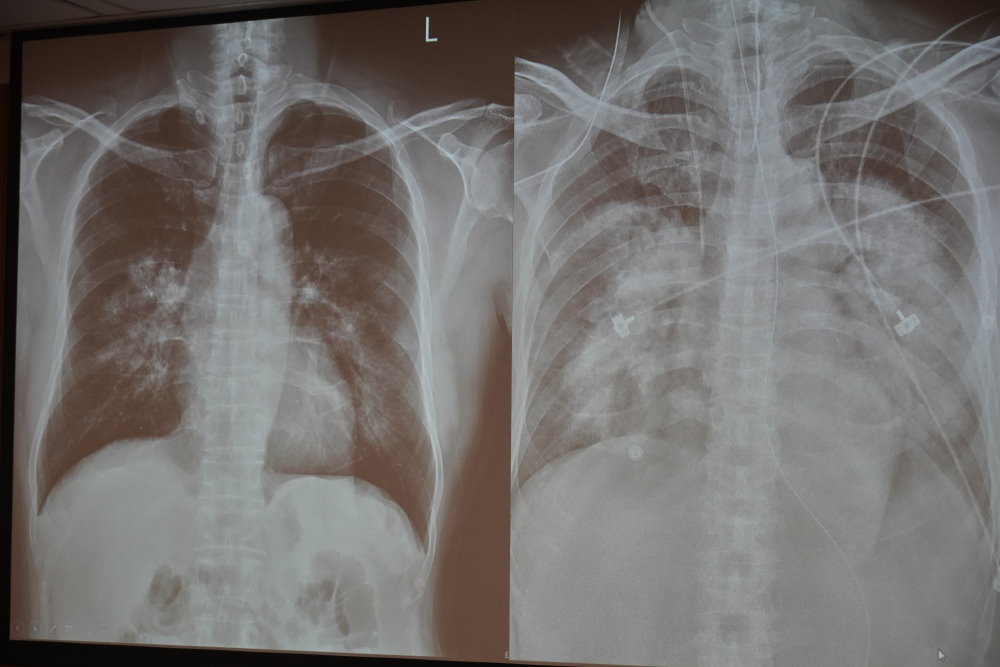

【記者田進山/台南報導】南市一位64歲有糖尿病的伯伯,因上呼吸道症狀、咳嗽、發燒、呼吸喘至醫院就診,發現雙側大片肺浸潤及呼吸衰竭,進行氣管內管插管並使用呼吸器,由於病情嚴重程度,轉至成大醫院繼續治療。經檢查確診為新冠肺炎引發的急性呼吸窘迫症候群(ARDS),治療期間出現低血氧、麴菌肺炎、縱膈腔氣腫、肺栓塞等多種併發症,陸續使用俯臥通氣、抗生素、抗凝血劑、氣切造口等措施,經過兩個多月的治療,伯伯順利出院恢復日常生活。

ARDS的診斷標準主要為胸部影像學(X光或電腦斷層)和柏林定義 (Berlin Definition) 。影像學通常顯示雙側瀰漫性的肺浸潤,也有人稱為「大白肺」。柏林定義則包括急性發病時間為7天內,並根據氧合指數 (PaO2/FiO2) 將疾病嚴重程度分成輕微 (200-300)、中度 (100-200)與重度 (<100)。